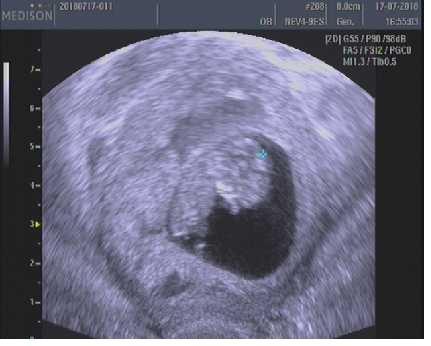

@veronika_2019 včera 10+1, takže dnes 10+2. Podle koníka jsem o den dopředu, ale podle maminkam.cz jsem přesně jak říká pán doktor 🙂

@kristynkal takže jsme na tom skoro stejně 😀 já teda podle MS 11+0 a podle UTZ 10+3, ale měla jsem vždy opozdenou ovulaci i MS 🙂